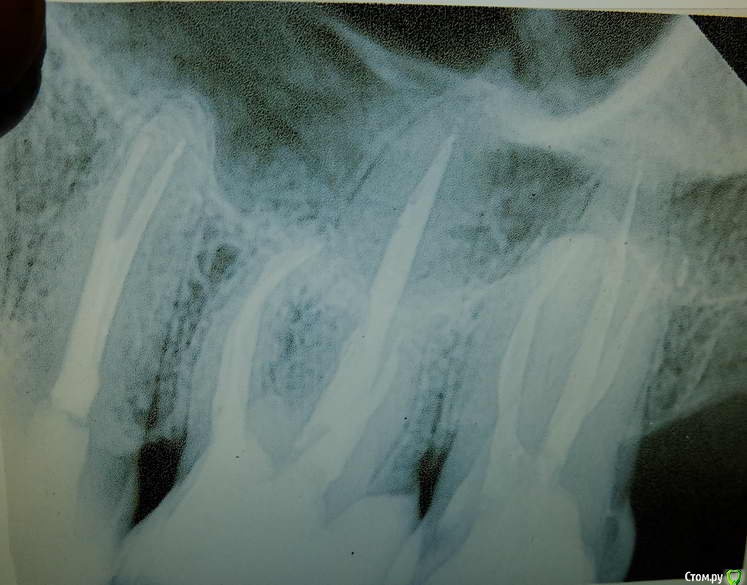

lejeboka Опубликовано 10 мая, 2018 Поделиться Опубликовано 10 мая, 2018 (изменено) Добрый день На днях сходил к стоматологу на контрольных осмотр и проф гигиену. Лечусь у нее с 2010 года, в общем доверяю. Результат расстроил.6-й слева снизу – на удаление.Зуб был депульпирован в 1990-м, в райполиклинике, спустя 2-3 года поставил коронку там-же. Успешно проходил с ней 17 лет, потом решил поменять на металлокерамику. Врач-ортопед ставить коронку отказался, т.к. были изменения на корнях.Переделали каналы. Спустя 6 лет – киста, культевую вкладку удалить нельзя, зуб на удаление. https://cloud.mail.ru/public/JuP9/LF2BUBPsG https://cloud.mail.ru/public/9mas/cnXZ2Ra6JСедьмой справа сверху – необходимо ставить коронку, т.к. пломба выпала, и качественно ее поставить нельзя. Зуб был депульпирован в 2011-2012 году лечащим врачом. Но нужно переделать один из каналов. https://cloud.mail.ru/public/7fhp/wFFS5S6S4 Седьмой снизу (рентгена нет) , справа, поставлена коронка 6 лет назад коронку надо менять, т.к. десна опустилась. Вопрос 1: нормально ли это, что спустя 5-7 лет после депульпирования нужно переделывать каналы, а после ревизии каналов зуб идет на удаление? Каналы были запломбированы хорошо, в чем тогда проблема, в стерильности при работе?Прошу прощения перед доктором, если она вдруг читает этот форум.Еще у нас был пропущеный канал на одном из зубов и киста. В след четверг записался на удаление левой нижней шестерки.Вопрос 2, извините если слишком ламерский. Как я понимаю, при удалении зуба при планах на последующую имплантацию иногда в лунку добавляют какой-то материал для того, что бы кости было больше. Это нужно обсуждать с доктором перед удалением? Доктору нужно будет передать рентгеновский снимок? Вопрос 3: правильно я понимаю, что на корнях 7-ки снизу слева то-же есть проблемы? Изменено 10 мая, 2018 пользователем lejeboka Ссылка на комментарий